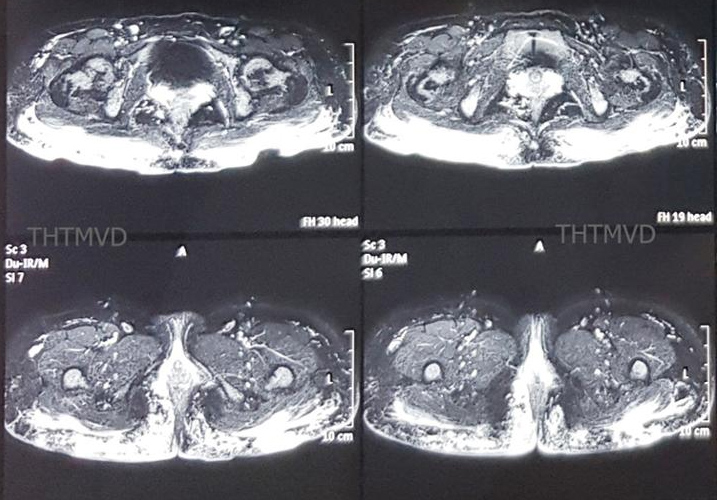

PGS.TS Nguyễn Hồng Hà, Trưởng khoa Phẫu thuật – Tạo hình – Thẩm mỹ, Bệnh viện Hữu nghị Việt Đức cho biết, bệnh nhân vào viện trong tình trạng mệt mỏi, lo lắng, thiếu máu nhẹ. Vùng mông có hiện tượng viêm sưng nề nhiều, xen kẽ các vết thủng loét đã vỡ rò chảy mủ ra ngoài. Phim chụp cộng hưởng từ MRI 3.0 cho thấy, hàng trăm khối u siliconoma cùng hiện tượng viêm lan tỏa trong lớp da cơ mông và thâm nhiễm đến gần hậu môn.

Phim cộng hưởng từ cho thấy viêm tấy lan tỏa. (Ảnh: Bệnh viện cung cấp)